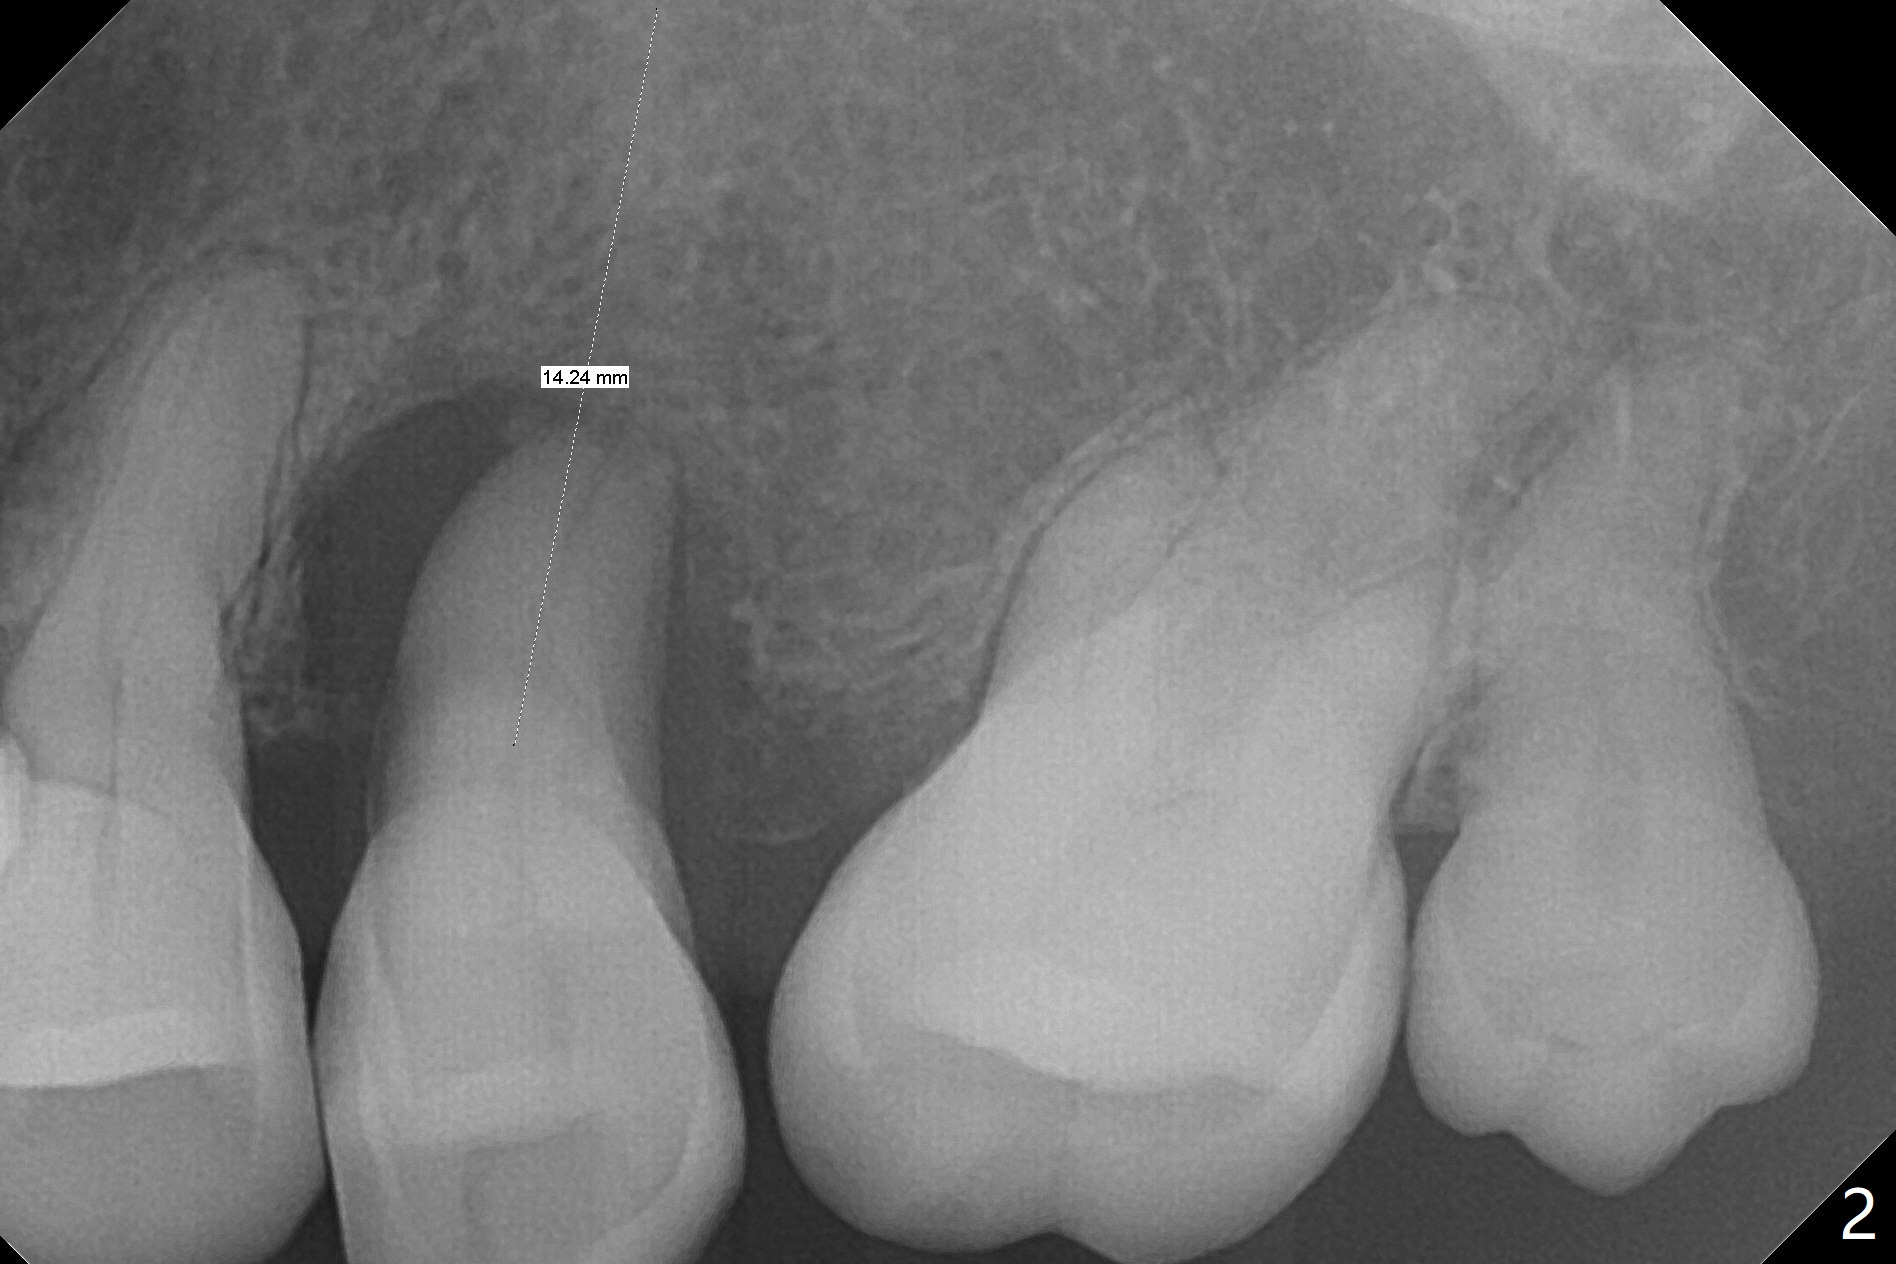

A 82-year-old woman without history of osteoporosis (regular exercises) has poor dentition (Fig.1). Her concern is a loose tooth at #13 (Fig.2). The bone available for implantation seems to be unlimited (Fig.3, taken 3 years earlier). The longest implant will be used to compensate for low bone density, if there is no osteoporosis. Since the bone loss is severe, a bone-level implant provides flexibility in choosing an abutment with various length of the cuff (including mill abutment).